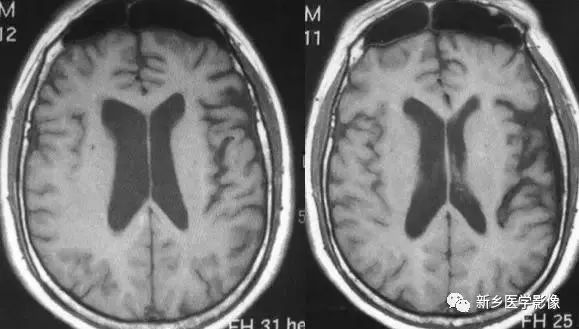

❶ 普遍性脑萎缩

普遍性脑萎缩常同时累及灰质和白质,可表现为双侧侧脑室扩大,而且是双侧侧脑室轻度对称性扩大最常见的原因。尤其多见于以脑白质萎缩为主的病人。

普遍性脑萎缩引起的侧脑室扩大通常比较对称,中线无移位。其特点是同时有脑沟、脑裂增宽等脑皮质萎缩的表现。

普遍性脑萎缩可见于正常老年人。